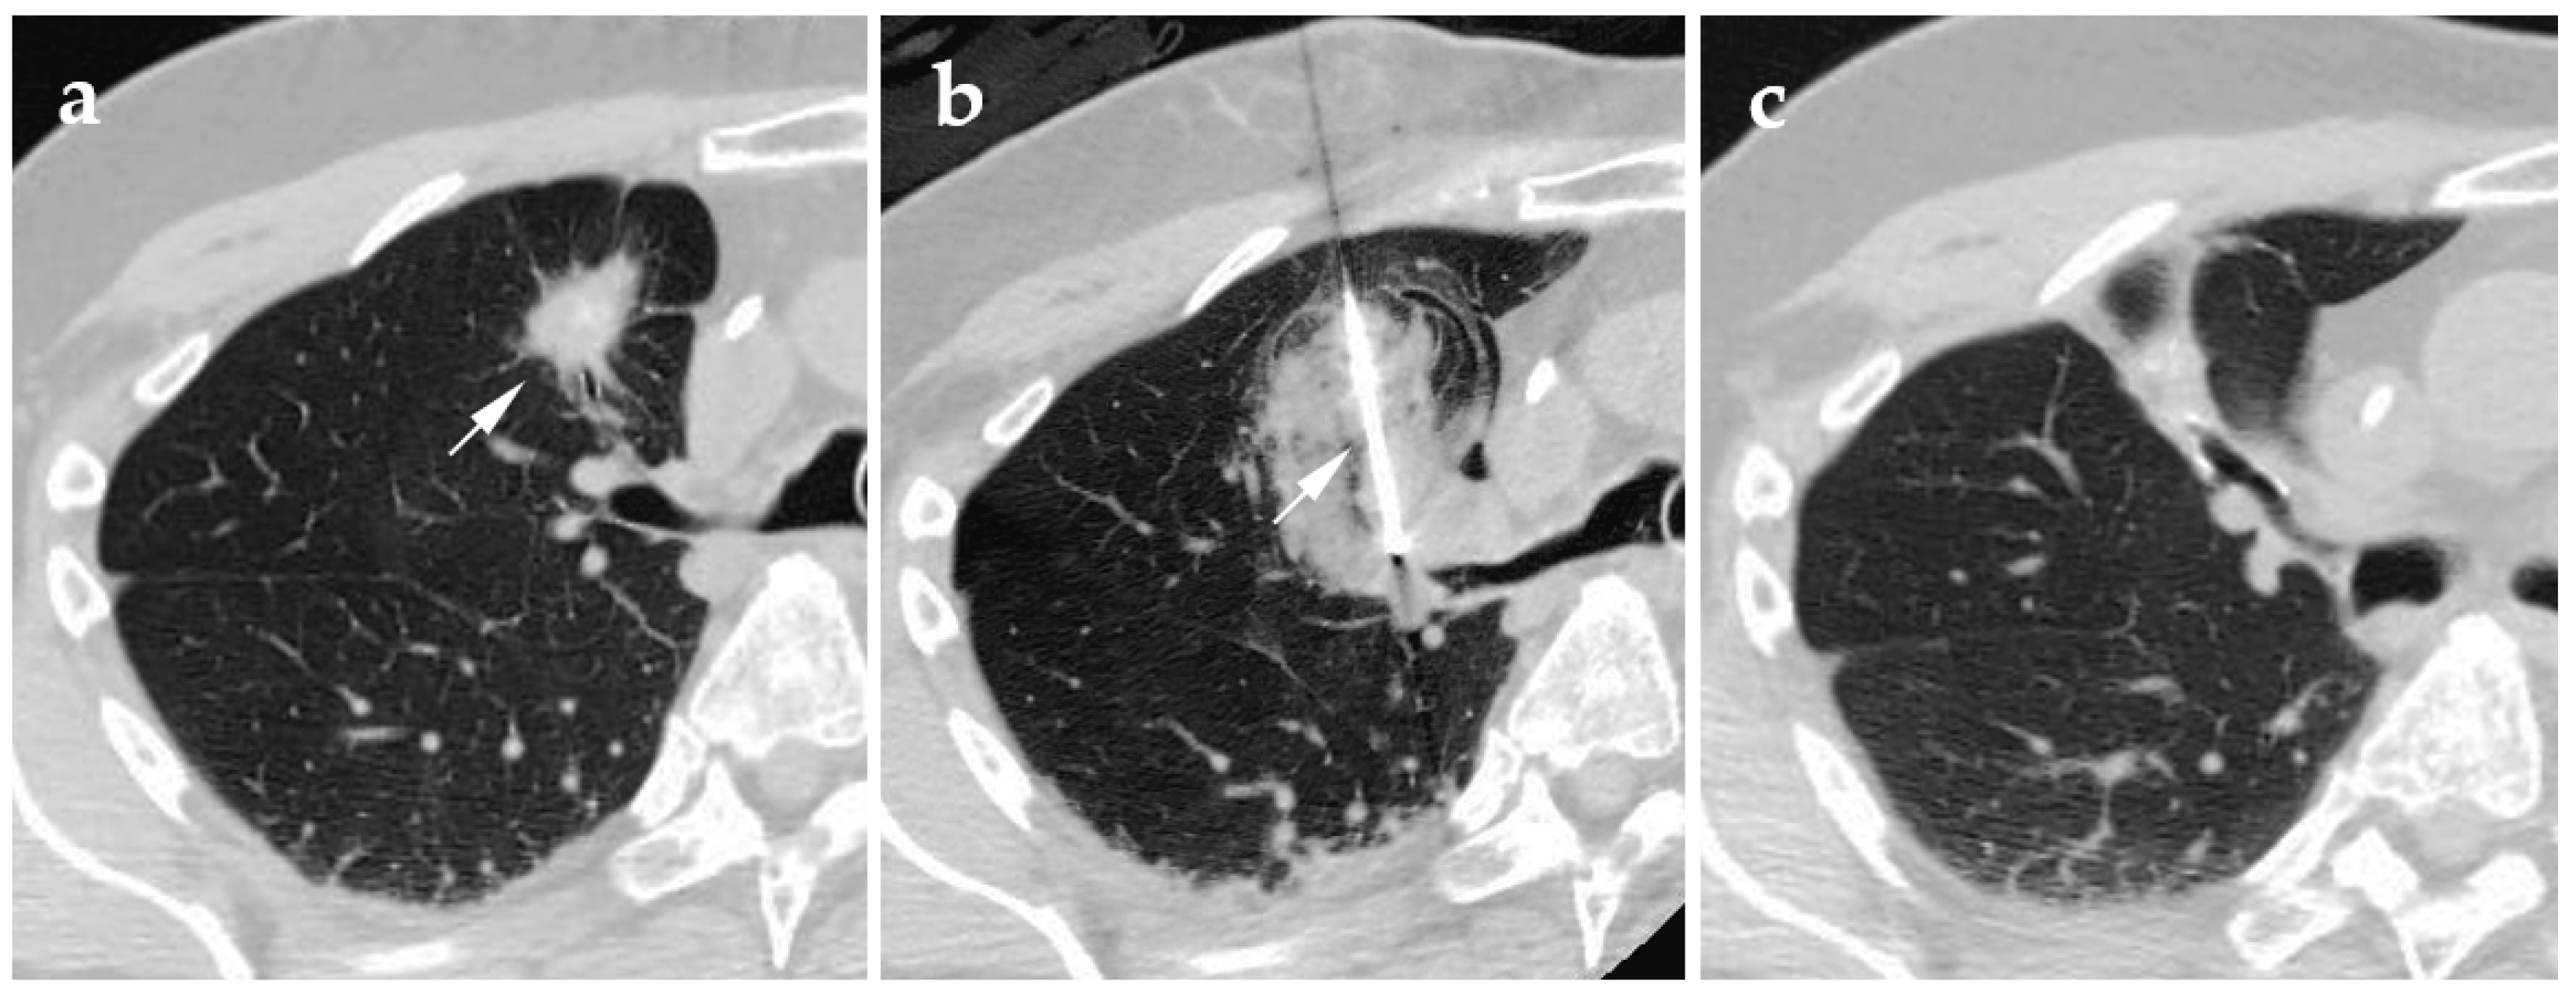

4.3. Microwave Ablation